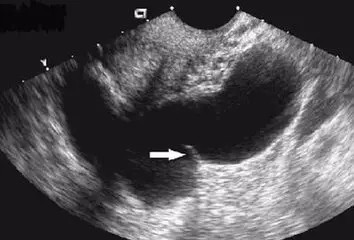

输卵管积水

252x192 - 40KB - JPEG